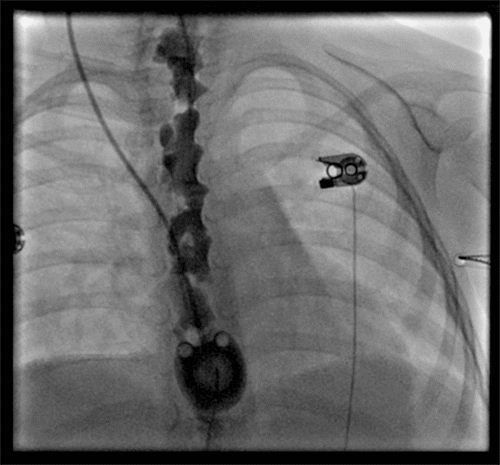

After the procedure, a chest X ray (Figure 1) confirmed the seemingly successful placement of the CVC chemo-port; the patient was transferred to the pediatrics team for postoperative monitoring. Over the next few days, the port never functioned correctly. A minimal amount of blood was able to be aspirated from the port. While it seemed to flush well, the patient would complain of severe pain when normal saline flush was injected through the port. The pain was described as being all over her body. She could not be distracted from the pain, which reportedly stopped as soon as the flush was stopped. Although no IV medication was ever administered through the port, injection of TPA was performed through the port due to a concern of sluggish blood draw from the port, which did not improve with a blood draw. Due to concern for a malpositioned port, interventional radiology was consulted and performed a port contrast study (Figure 2 and Figure 3) which revealed that the catheter was located in the epidural space, which was confirmed by a CT scan (Figure 4). The port was immediately removed while the patient was sedated in the radiology suite.

Figure 3. Contrast in Epidural Space. Published with Permission

Contrast in Epidural Space